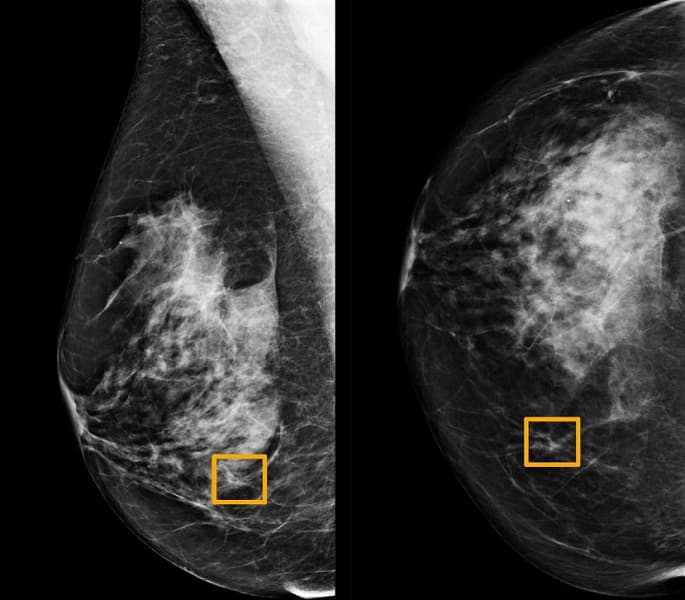

Искусственный интеллект Google выявляет рак груди точнее опытного врача

Исследование, опубликованное в журнале Nature, показало, что искусственный интеллект (ИИ) может повысить точность скрининга на рак молочной железы, которым, как утверждается, страдает каждая восьмая женщина в мире. Изучая маммограммы, система искусственного интеллекта Google показала себя не хуже, чем опытные врачи…